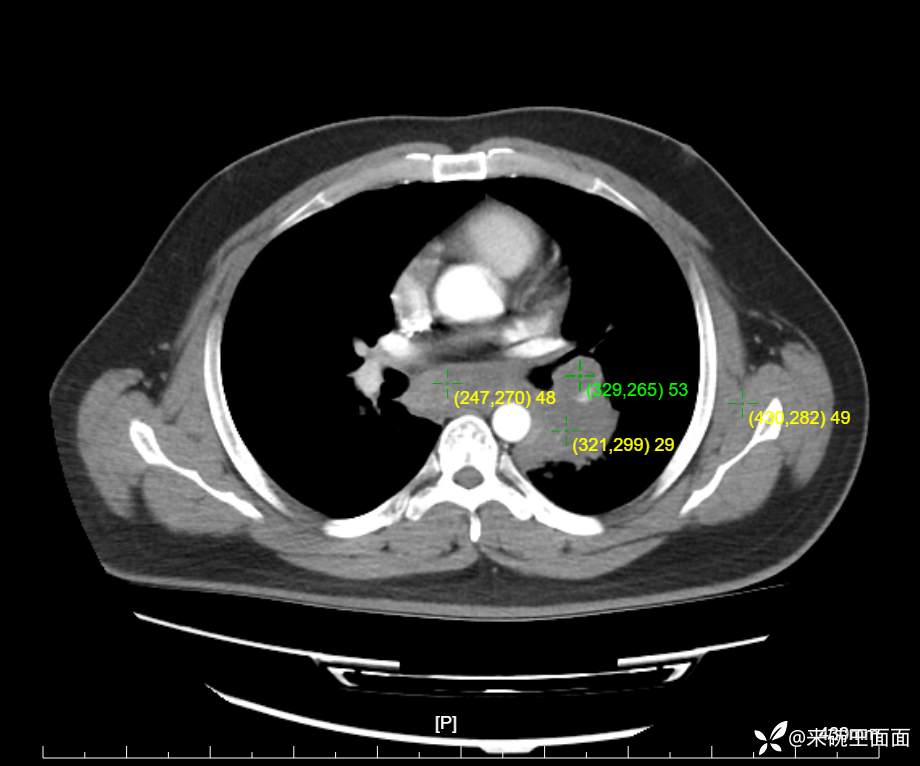

性别:男

年龄:27岁

主诉:胸闷胸痛数月余,休息后可自行缓解,无咯血症状。

个人史:数年吸烟史,具体不详。